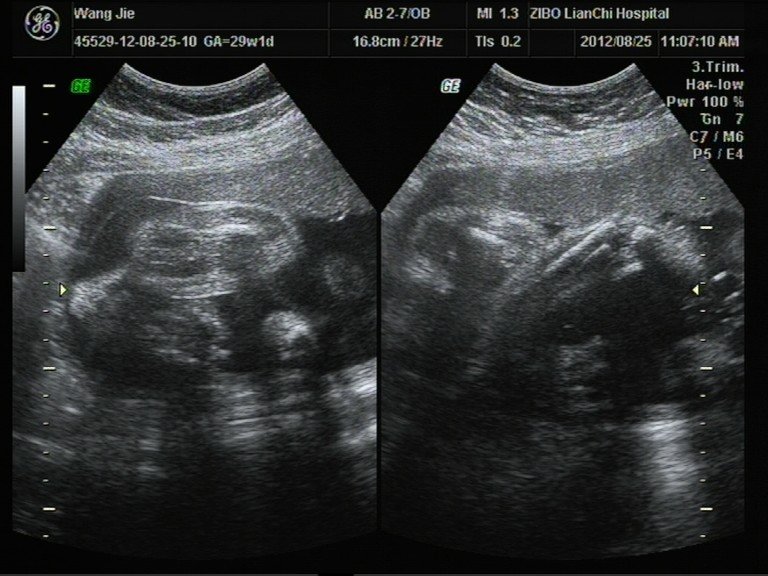

患者信息:女 29岁 病情描述(发病时间、主要症状等):彩超数据和相关照片,想知道宝宝男女。其余大部分照片在我百度空间的相册中。想得到怎样的帮助:想知道宝宝性别。曾经治疗情况及是否有过敏、遗传病史:四维彩超不清楚发哪张好。其余在我的百度空间中。

楼主,你的图像太模糊了,还是去找个认识的医生叫他帮你再看看吧。 四个半月